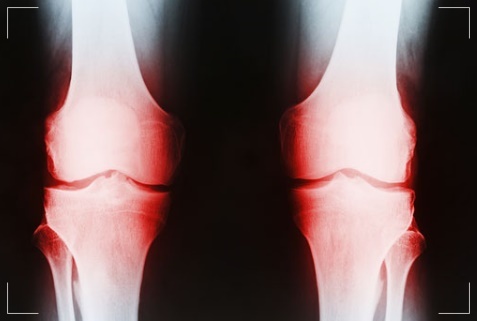

무릎 퇴행성관절염은 무릎의 연골(물렁뼈)이 닳아 없어지며 염증이 발생하는 질환입니다. 무릎을 오랫동안 사용해 온 노년층에서 많이 발병합니다. 하지만 요즘은 젊은 층에서도 퇴행성관절염으로 고생하고 있는 사람들이 많습니다. 방치하면 퇴행성관절염의 증상과 치료방법에 대해 확인하시기 미리 예방하시기 바랍니다.

퇴행성관절염은 시간이 흐를수록 연골 손상 범위가 넓어집니다. 퇴행성관절염을 방치해 무릎 위아래 뼈가 맞닿을 정도로 연골이 손상되면 관절 전체를 인공관절로 대체해야 합니다. 퇴행성관절염은 서서히 진행되는 탓에 병을 인지하지 못해 방치하기 쉬운데 초기에 발견해 치료하면 진행 속도를 늦출 수 있습니다.